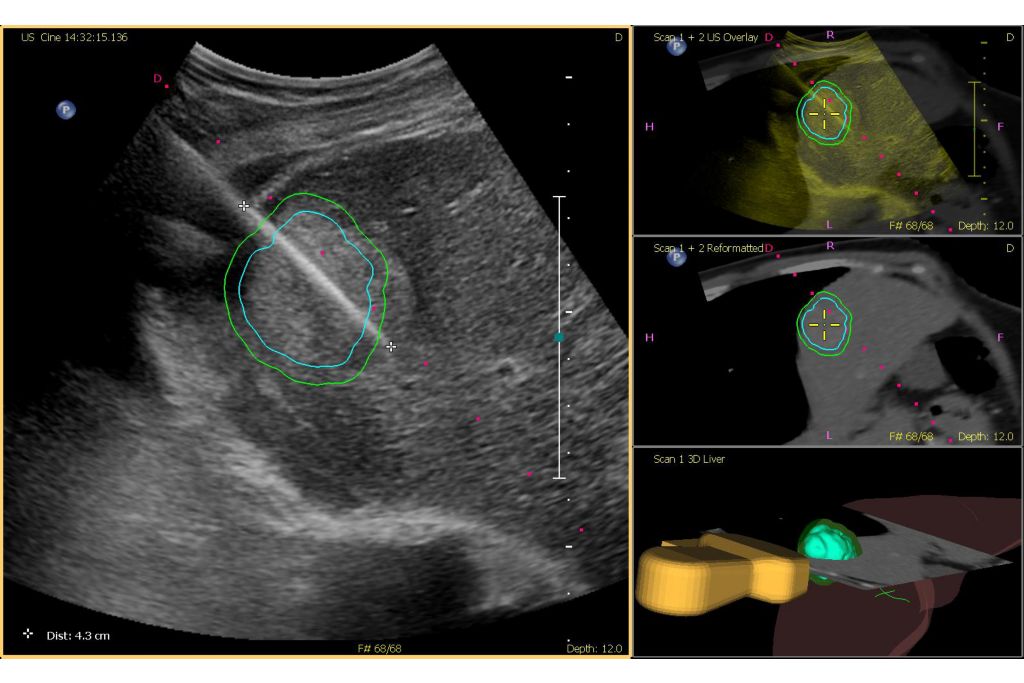

Outline a 3D contour to help visualize your target

Tumor contour is a semi-automated tool that helps outline a 3D contour around a structure of interest. The clinician can easily plan and target a lesion during an interventional procedure, and help improve procedure guidance even in challenging cases where the lesion may not be visually obvious under ultrasound. The lesion can be rendered in 3D or 2D via a complementary modality and overlaid on the live ultrasound or CT, helping visualize the location in relation to surrounding critical structures.